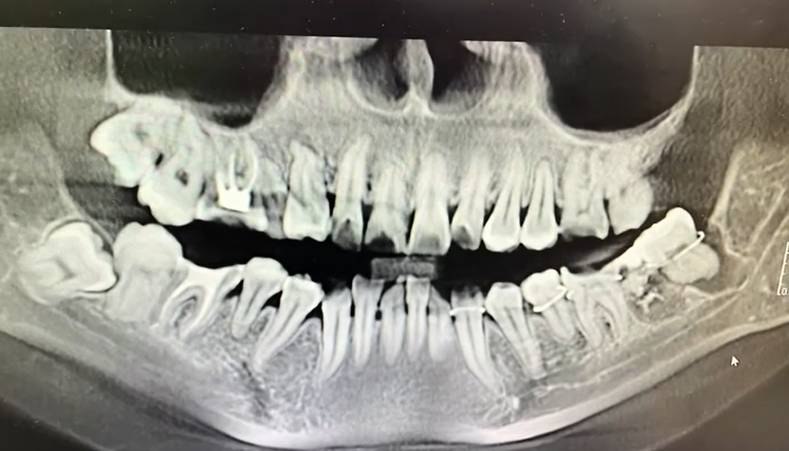

12 ΠΌΠ°ΡΡΠ° ΠΏΠ°ΡΠΈΠ΅Π½ΡΠΊΠ° ΠΎΠ±ΡΠ°ΡΠΈΠ»Π°ΡΡ Π² ΡΡΠΎΠΌΠ°ΡΠΎΠ»ΠΎΠ³ΠΈΡΠ΅ΡΠΊΠΎΠ΅ ΠΎΡΠ΄Π΅Π»Π΅Π½ΠΈΠ΅ ΠΠ½ΡΡΠΈΠ½ΡΠΊΠΎΠΉ Π³ΠΎΡΠΎΠ΄ΡΠΊΠΎΠΉ Π±ΠΎΠ»ΡΠ½ΠΈΡΡ Π΄Π»Ρ ΡΠ΄Π°Π»Π΅Π½ΠΈΡ Π·ΡΠ±Π° ΠΌΡΠ΄ΡΠΎΡΡΠΈ. ΠΡΠ°Ρ ΡΠ»ΡΡΠ°ΠΉΠ½ΠΎ Π²ΡΡΠ²Π°Π» Π·Π΄ΠΎΡΠΎΠ²ΡΠΉ Π·ΡΠ±, Π·Π°ΡΠ΅ΠΌ Π²ΡΡΠ°Π²ΠΈΠ» Π΅Π³ΠΎ ΠΎΠ±ΡΠ°ΡΠ½ΠΎ ΠΈ Π·Π°ΡΠΈΠΊΡΠΈΡΠΎΠ²Π°Π» ΠΏΡΠΎΠ²ΠΎΠ»ΠΎΠΊΠΎΠΉ, Π½Π΅ ΠΏΡΠ΅Π΄ΡΠΏΡΠ΅Π΄ΠΈΠ² ΠΏΠ°ΡΠΈΠ΅Π½ΡΠΊΡ.

ΠΠ΅Π½ΡΠΈΠ½Π° ΡΠ·Π½Π°Π»Π° ΠΎ ΡΠ»ΡΡΠΈΠ²ΡΠ΅ΠΌΡΡ ΡΠΎΠ»ΡΠΊΠΎ ΠΏΠΎΡΠ»Π΅ ΠΏΠΎΡΠ΅ΡΠ΅Π½ΠΈΡ Π΄ΡΡΠ³ΠΎΠΉ ΠΊΠ»ΠΈΠ½ΠΈΠΊΠΈ. Π‘ ΠΌΠΎΠΌΠ΅Π½ΡΠ° ΠΎΠΏΠ΅ΡΠ°ΡΠΈΠΈ ΠΎΠ½Π° ΡΡΡΠ°Π΄Π°Π»Π° ΠΎΡ ΡΠΈΠ»ΡΠ½ΠΎΠΉ Π±ΠΎΠ»ΠΈ, Π½Π΅ ΠΌΠΎΠ³Π»Π° Π΅ΡΡΡ ΠΈ ΠΏΠΎΡΡΠΈ Π½Π΅ ΡΠΏΠ°Π»Π° ΠΏΡΡΡ Π΄Π½Π΅ΠΉ.